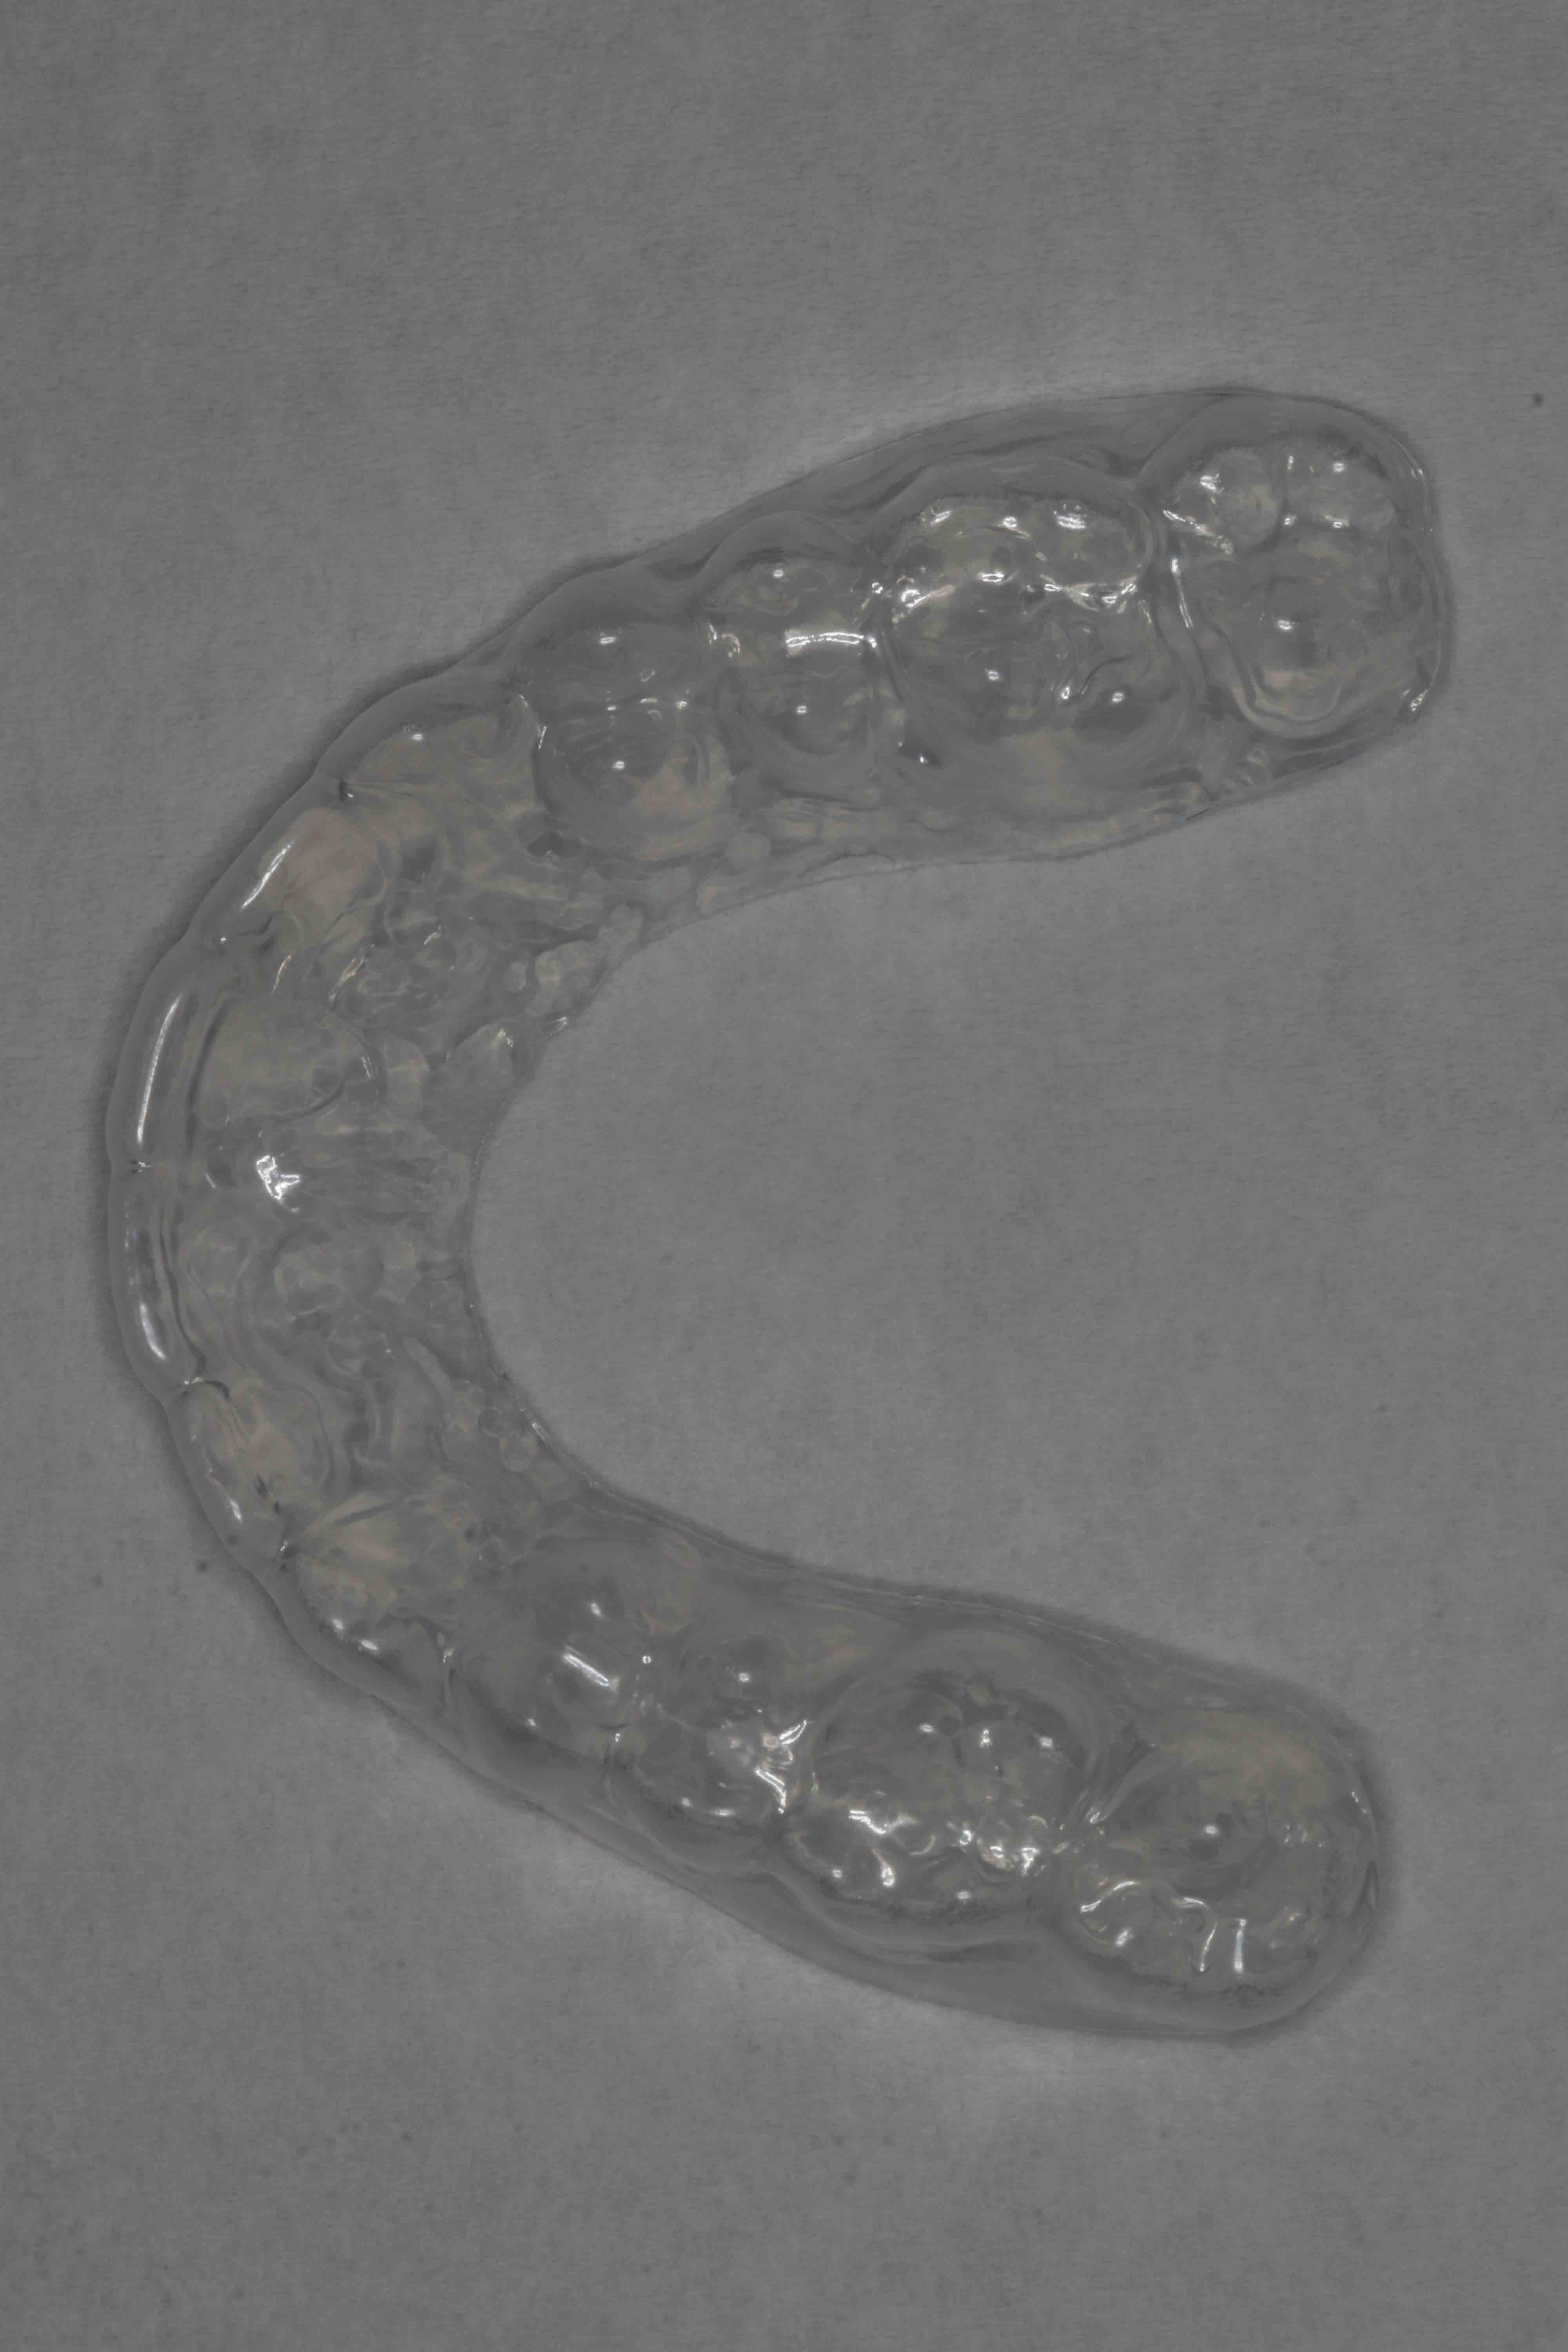

Etter avsluttet aktiv behandling med streng legges det vekt på å bevare resultatet. Pasienten får retensjonsutstyr etter instruksjon, med plater og strenger i både over- og underkjeven. Videre oppfølging avtales for å sikre stabil tannstilling. Pasient og foresatte innkalles til gjennomgang av behandlingen.